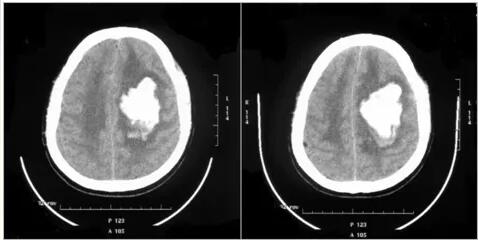

联系到林先生的家属后,同事紧急将他送往当地医院,其头颅CT提示左侧放射冠-半卵圆中心区脑出血,出血量约70ml。

(图:外院CT影像)